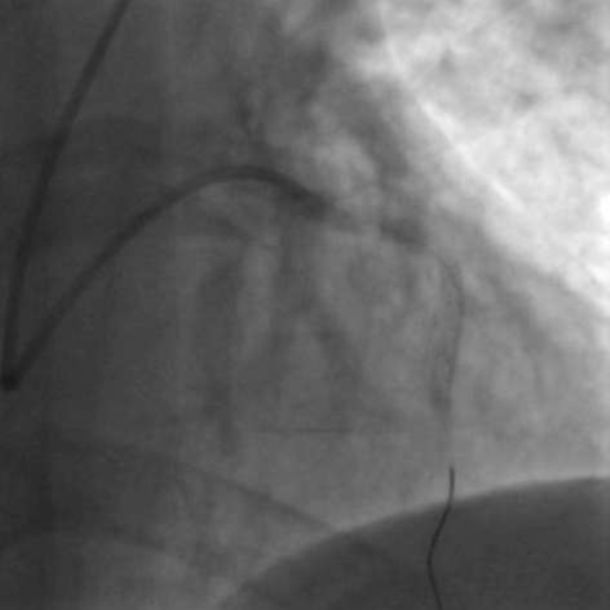

右桡动脉入路时,JR指引导管头端往往略向下,不易与右冠近段同轴,支撑力极其有限,因此右桡动脉入路时可以考虑首选TR指引导管(TR4.0通常能适应绝大多数患者)。由于导管头端的形状以及泰尔茂指引导管整体偏软,TR指引导管的支撑力也较弱。当右冠状动脉开口后朝上走形呈牧羊钩状时,TR的导引导管往往也不能提供足够的支撑力,此时可选用AL指引导管(图十二)或XBRCA指引导管(图十三)。

图十二 AL指引导管进入右冠